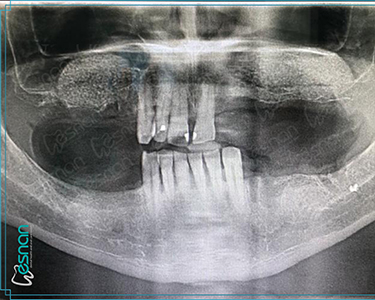

Oral, dental, and maxillofacial radiology is a crucial element in comprehensive dental care. It utilizes various imaging techniques, such as periapical radiographs, panoramic radiographs, cone beam computed tomography (CBCT), and occlusal radiographs. These tools provide valuable insights into the underlying structures of the mouth, teeth, and jaws, allowing dentists to diagnose and treat a wide range of conditions, including dental caries, periodontal disease, infections, tumors, and developmental abnormalities. Early detection and accurate diagnosis through oral, dental, and maxillofacial radiology can significantly impact treatment outcomes and improve overall oral health.

Oral symptoms usually have underlying bone and skeletal structures beneath the soft tissues. Radiographs can reveal structures that are not clinically visible, helping dentists to deal with many unidentified problems. The advantages and applications of oral, dental, and maxillofacial radiology can be listed as follows:

• Planning for dental implants

Each examination listed above serves a specific purpose in dental diagnostics. Panoramic X-rays provide a broad view of your teeth, jaws, and surrounding structures, while intraoral radiography offers detailed images of individual teeth. Cephalometric X-rays assess facial growth and development, and CBCT scans provide detailed 3D images for complex cases like implant planning and oral surgery. Our experienced team is dedicated to utilizing these technologies to deliver precise and personalized care for every patient.